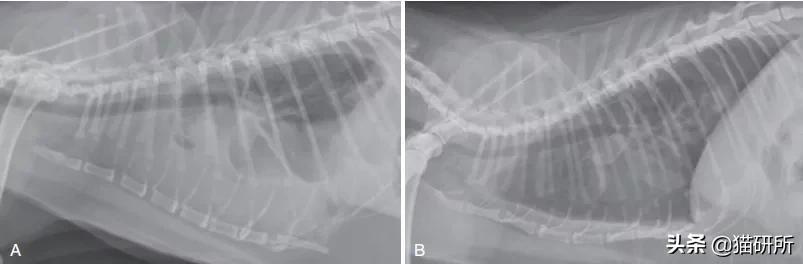

➤ 影像学检查:通过X线检查确定猫猫是否存在胸腔积液

A 胸腔积液的猫猫 B 抽出胸腔积液后

通过胸腔穿刺,在1B图中猫猫左右两侧胸腔总共抽出300ml“草莓奶昔”样的乳糜液,之所以呈粉色是因为乳糜液中含有血液。